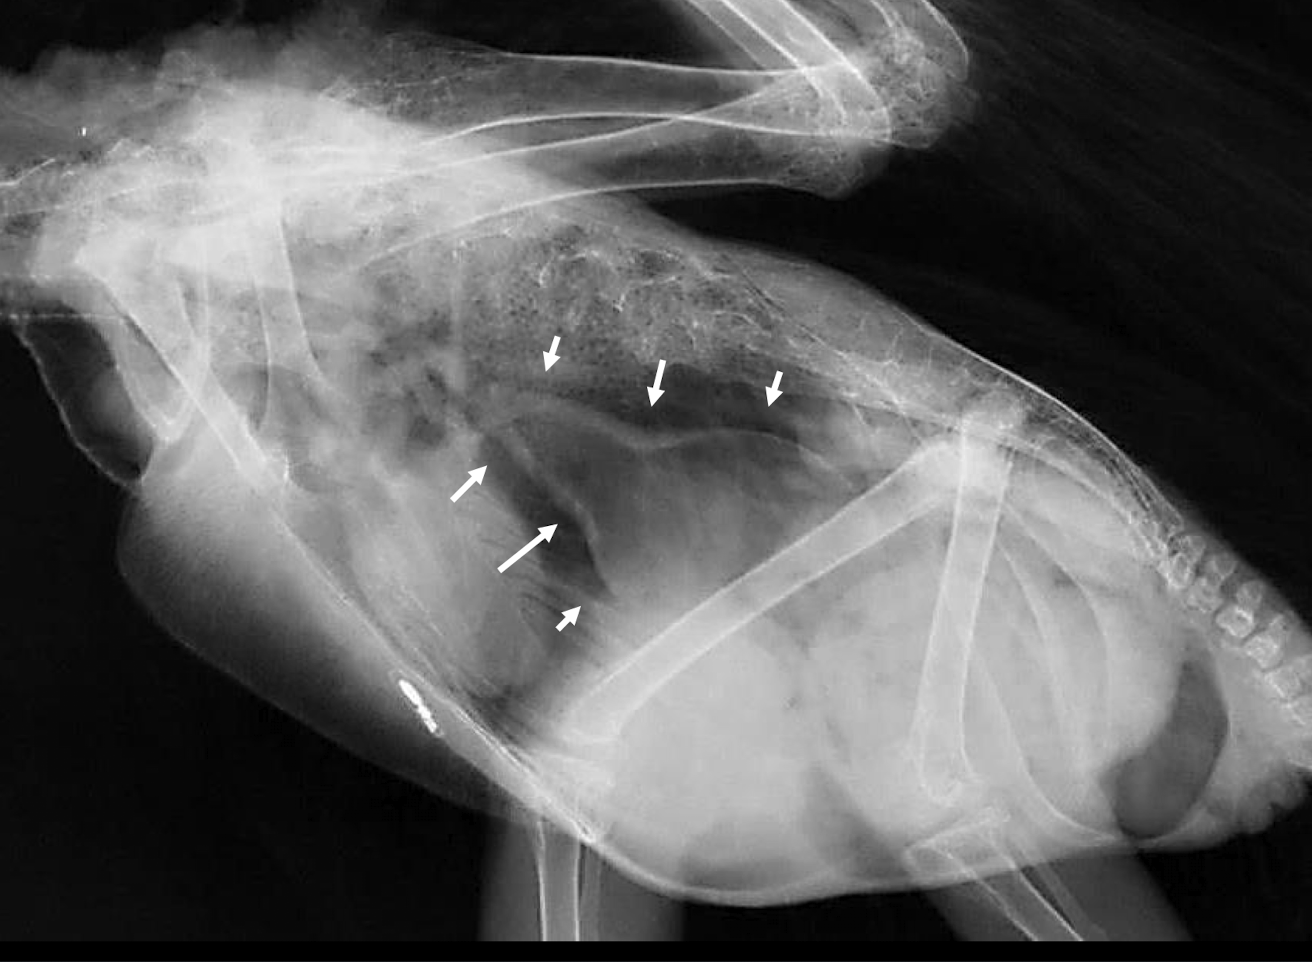

Whats wrong?

pneumonia

Bacterial airsacculitis → thickening of airsac wall

Fungal airsacculitis